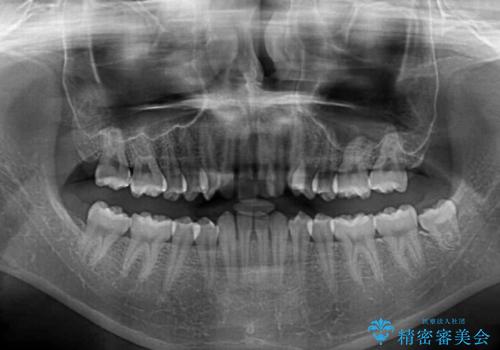

- 下顎前歯が欠損しており、前歯がデコボコとなっている歯並びを気にして来院された患者様です。

下顎の左右側切歯2本が欠損しており、上顎歯列がデコボコとなっている状態でした。

下顎歯列に対して上顎歯列が相対的に大きくなっているため、デコボコとなっているだけでなく、下顎前歯が見えなくなるくらいのディープバイトにもなっていました。